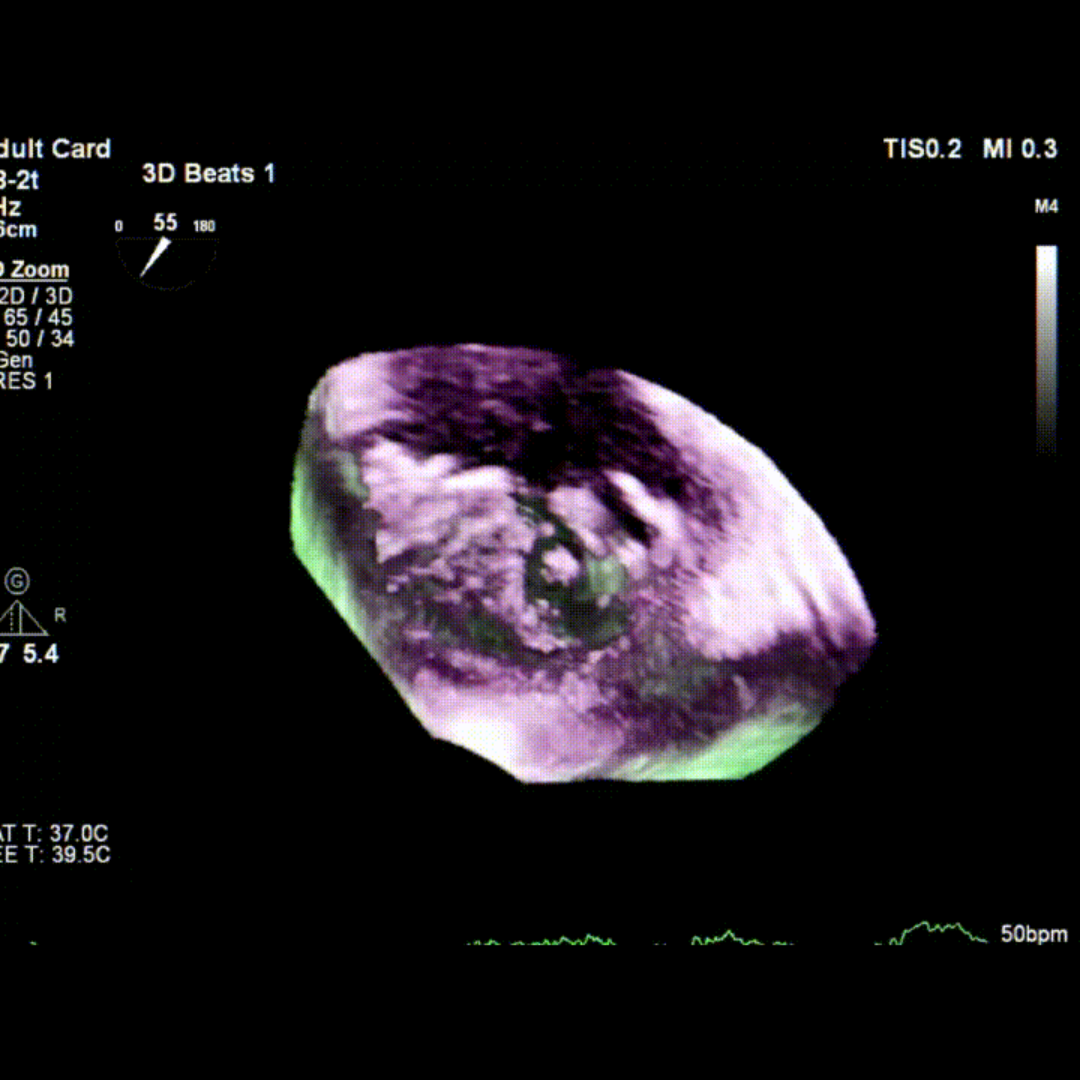

会议期间,张海波教授团队联合李伟教授完成了一例TA-TEER现场手术演示。患者为混合性二尖瓣反流(DMR+FMR),伴瓣环扩大、前瓣叶冗长、三区反流、后叶栓系及短小等复杂情况。术者在充分评估后选择置入双夹,手术获得圆满成功。现场专家就夹子型号选择、双夹放置位置及三区交界病变穿刺点等问题展开了深入讨论。

术前TEE影像

术中TEE影像